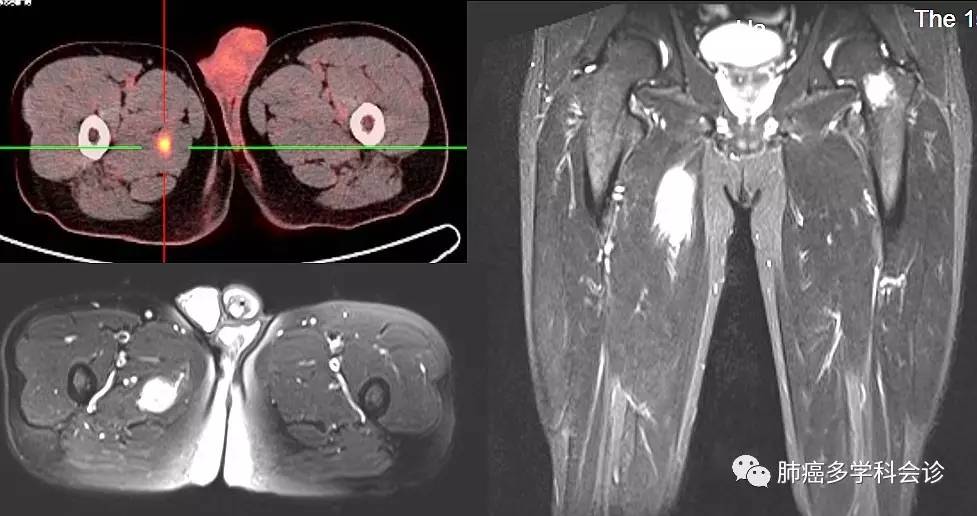

微信图片_20170817161858.jpg2017年2 ~ 4月 培美曲塞 + 顺铂化疗4周期后患者诉右侧大腿内侧疼痛。2017.04.21右侧大腿MRI检查结果回示:左股骨颈、右侧股骨近端水平内侧大收肌内异常信号,考虑转移瘤。微信图片_20170817161901.jpg右侧大腿穿刺活检病理:(右下肢肿物穿刺活检)转移癌,结合病史倾向粘液表皮样癌。微信图片_20170817161904.jpg

目前临床上常用的辅助检查有 CT、磁共振、超 声及正电子发射断层扫描(PET)。 常见的 CT 表现为边缘增强而中央低密度表现的肌肉内肿块,MRI 则表现为肿瘤广泛增强,中央有坏死灶,瘤周水肿, 最终明确诊断仍需依靠组织学检查。

本例患者术后PET-CT提示右侧大腿大收肌代谢活跃灶。但因患者无不适症状,临床未触及肿块,未行活检,后治疗过程中患者出现疼痛症状,MRI检查提示右侧股骨近端水平内侧大收肌内异常信号,怀疑转移瘤。活检证实为转移癌。此例提示我们:虽然骨骼肌转移癌罕见,但现代化检查技术能帮助发掘出你不曾见、想不到的临床表现。